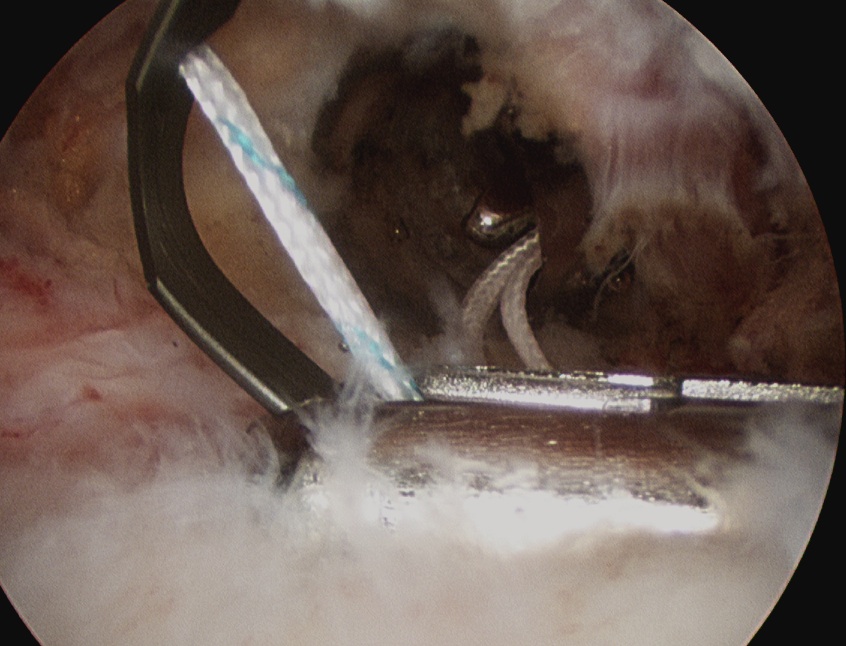

Tie sutures

- posterior to anterior / anterior to posterior

Double row

- either pass second lateral row of anchors or

- use foot print anchors, retrieve previous sutures

- can make suture bridge configuration

- check repair via lateral portal